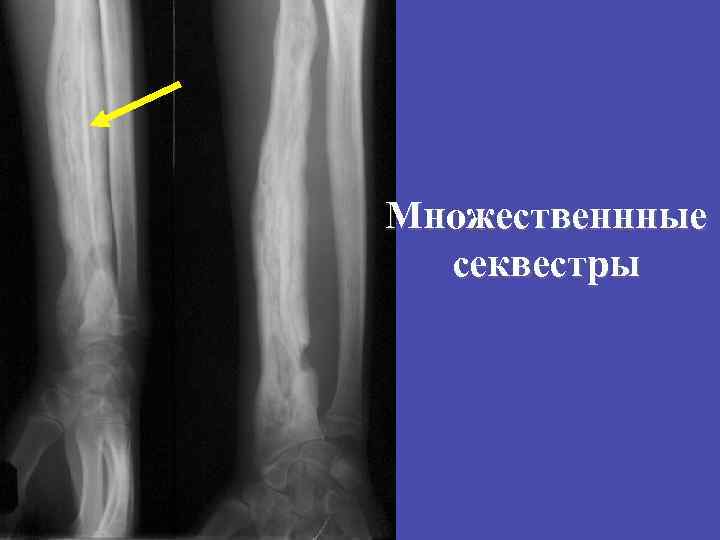

СЕКВЕСТРАЦИЯ Отторжение некротизированного участка. СЕКВЕСТР Изолированный фрагмент кости повышенной плотности

Множественнные секвестры

Слоистый периостит, секвестр в секвестральной полости метадиафиза большеберцовой кости 39

Слоистый периостит с переходом в гиперостоз, кортикальные секвестры плечевой кости 40